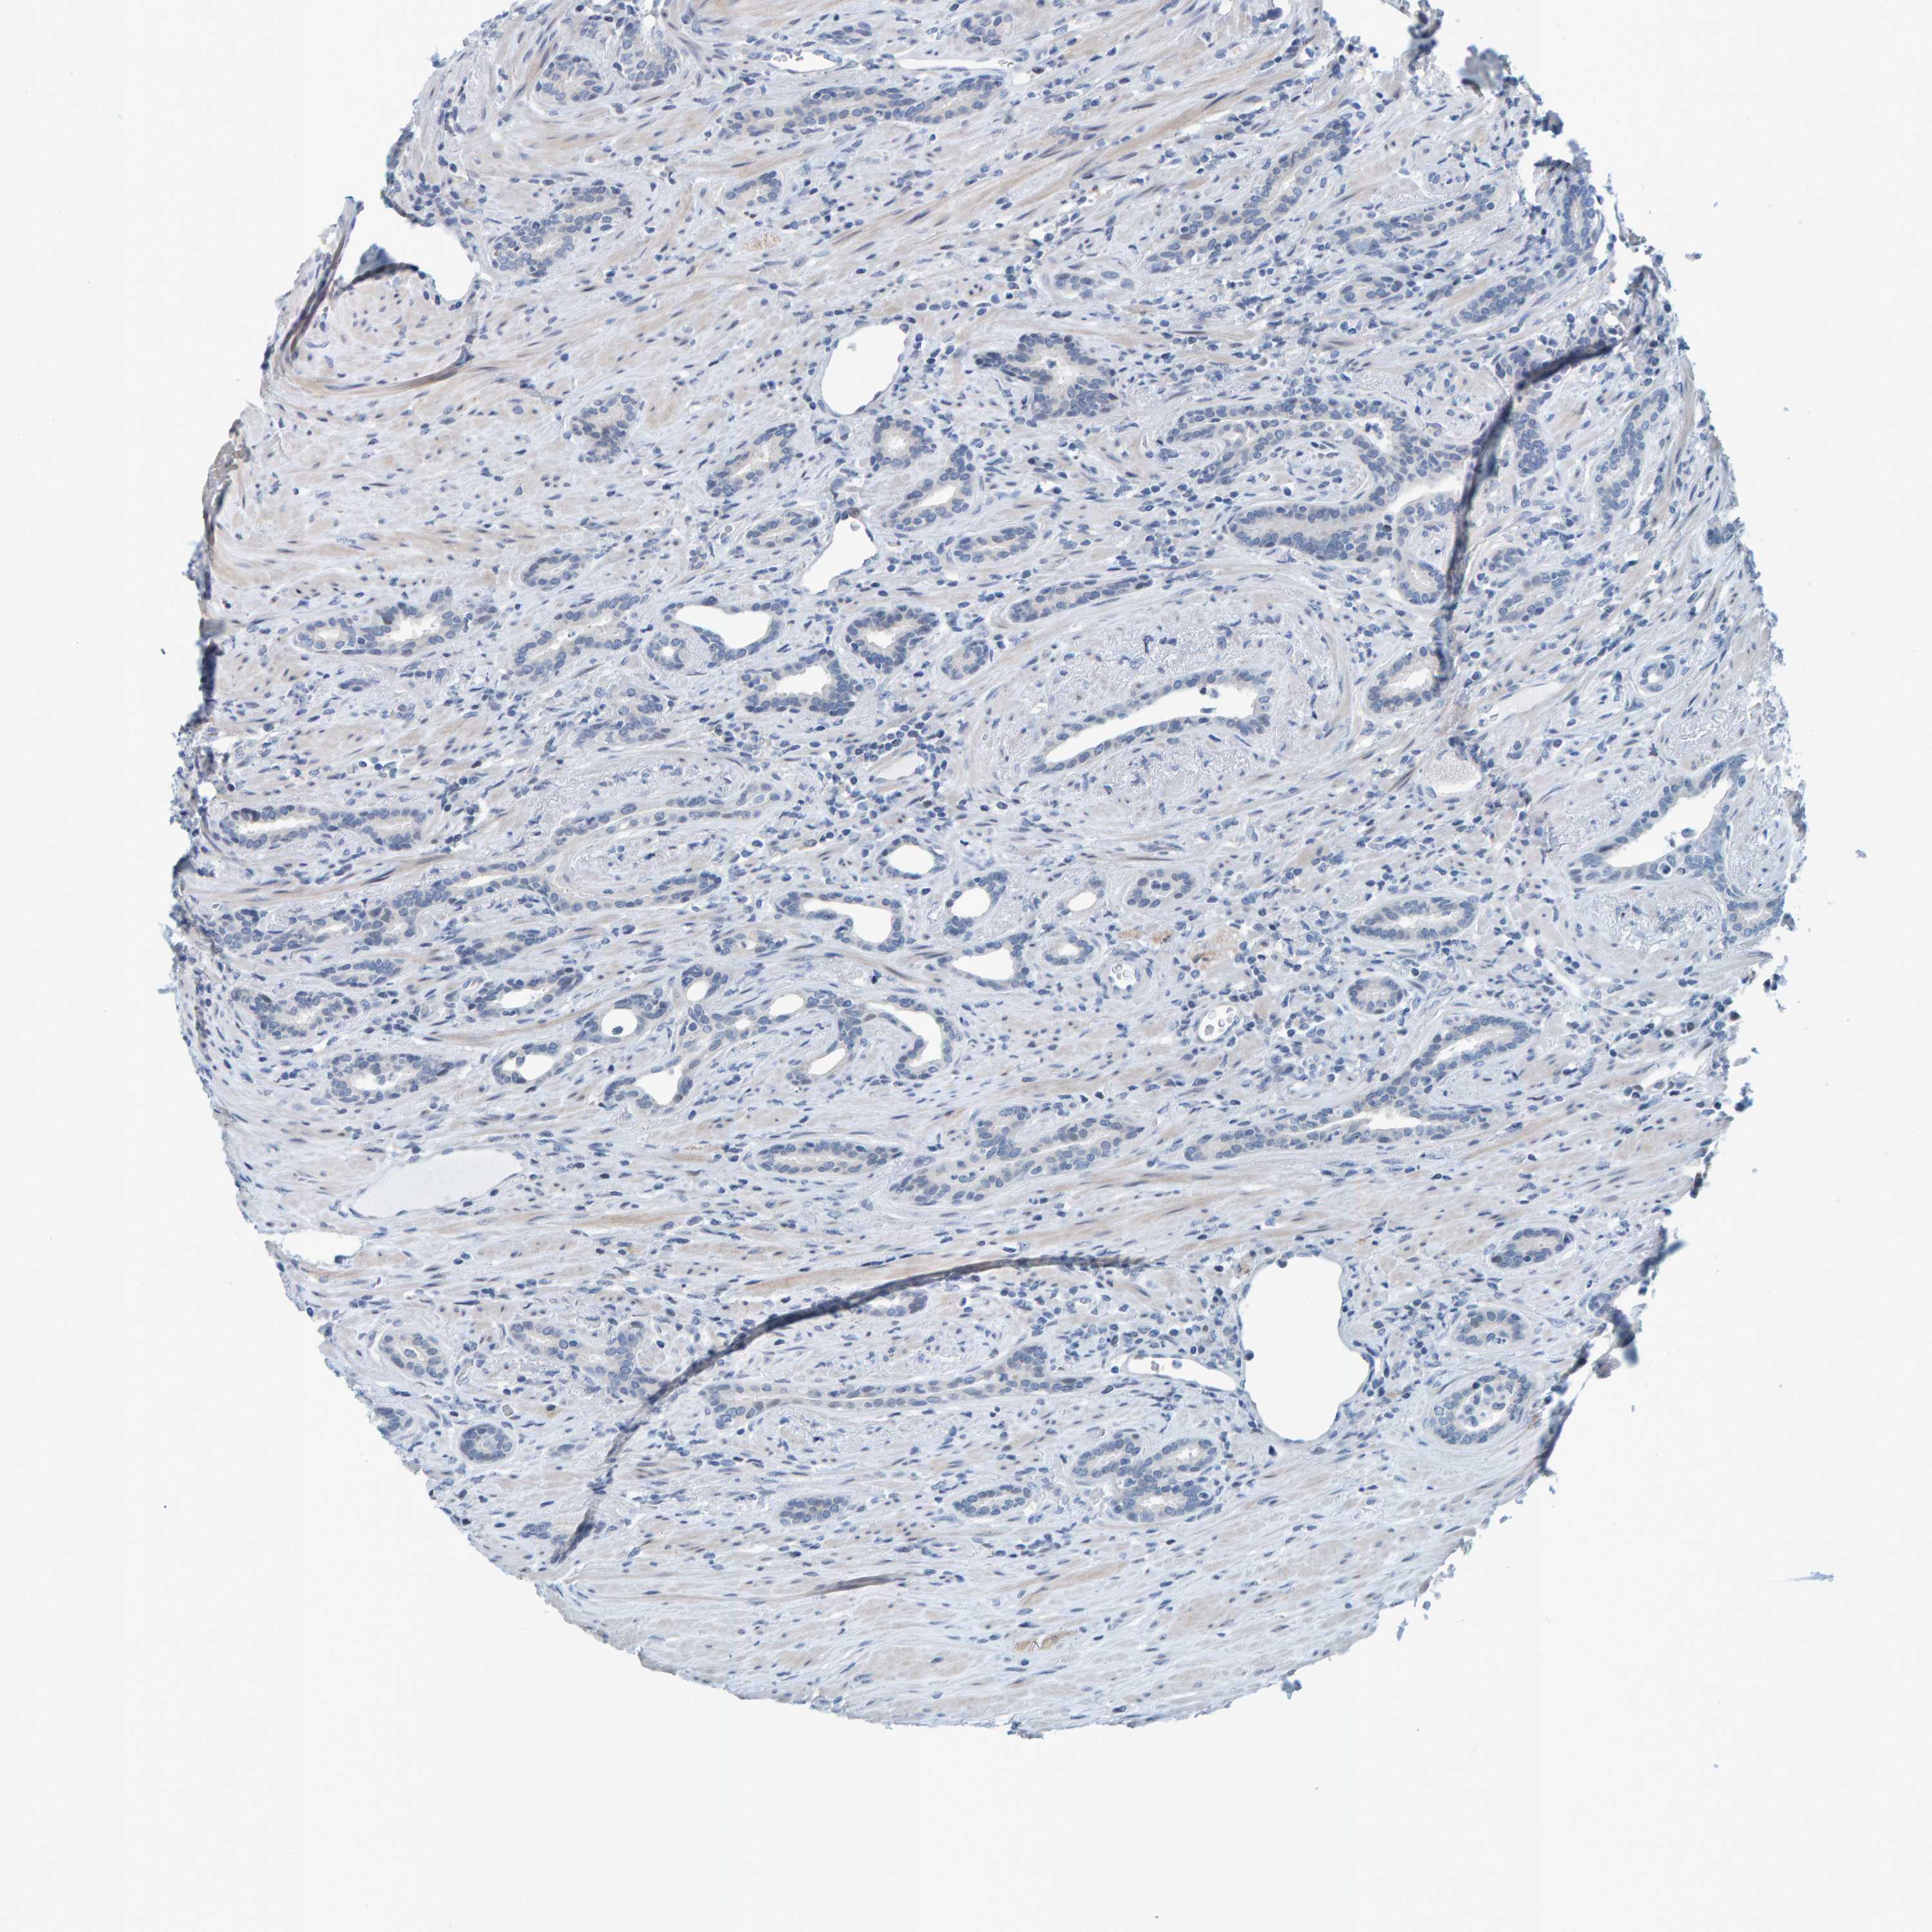

PROSTATE CANCER - Protein expressioni

A mouse-over function shows sample information and annotation data. Click on an image to view it in a full screen mode. Samples can be filtered based on level of antibody staining by selecting one or several of the following categories: high, medium, low and not detected. The assay and annotation is described here.

Antibody stainingi

Antibody staining in the annotated cell types in the current human tissue is reported as not detected, low, medium, or high, based on conventional immunohistochemistry profiling in selected tissues. This score is based on the combination of the staining intensity and fraction of stained cells.

Each image is clickable and will lead to virtual microscopy that enables deeper exploration of all samples and also displays staining intensity scores, fraction scores and subcellular localization as well as patient and tissue information for each sample.

HPA023266

HPA023278

HPA023280

HPA023338

CAB002672

Staining

High

Medium

Low

Not detected

Intensity

Strong

Moderate

Weak

Negative

Quantity

>75%

75%-25%

<25%

None

Location

Nuclear

Cytoplasmic/membranous

Cytoplasmic/membranous,nuclear

Adenocarcinoma, High grade

Adenocarcinoma, Low grade

Adenocarcinoma, NOS

Adenocarcinoma, Medium grade